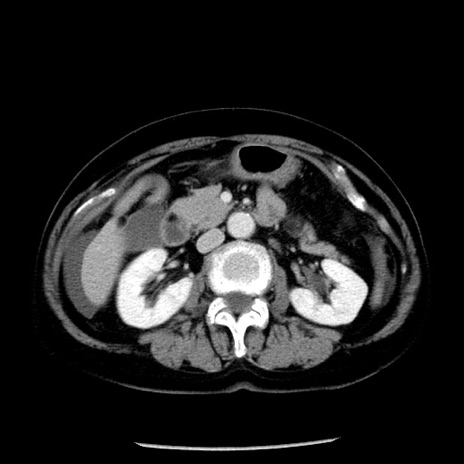

冠状断像

【症例】70歳代女性

【主訴】腹痛、嘔吐

【現病歴】15時間程前(昨晩)より腹痛あり。今朝になっても症状の改善なく、嘔吐あり。腹痛も増悪あり、救急外来受診。

【既往歴】子宮癌全摘術後

【身体所見】意識清明、BP 121/72mmHg、P 74bpm、SpO2 100%(RA)、腹部:平坦・軟、腸雑音ほぼ聴取せず。下腹部・心窩部・臍左上に圧痛あり。反跳痛なし。

【データ】WBC 10600、CRP 0.15